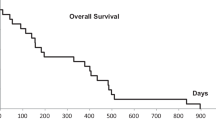

Median follow-up was 10.4 months (2.0–59.0 months). The 2‑year actuarial LC was 100 and 86.4% for primary early and advanced stage lung tumors, respectively, 100% for lung metastases, 82.2% for liver metastases, and 90% for extrapulmonary extrahepatic metastases. The 2‑year OS rate was 47.9% for all patients. In uni- and multivariate analysis, comparatively lower PTV prescription dose (equivalence of 3 × 12–13 Gy) and higher average GTV dose (equivalence of 3 × 18 Gy) to current practice were significantly associated with LC. For OS, Karnofsky performance score (100%), gender (female), and SBRT without simultaneous chemotherapy were significant prognostic factors. Grade 3 side effects were rare (0.5%).

The crude LC for all lesions (n = 280) was 92.9% at the time of analysis. The 2‑year actuarial LC was 100% for early stage primary lung tumors, 86.4% for advanced stage primary lung tumors (including re-irradiation of previously treated lesions), 100% for lung metastases, 82.2% for liver metastases, and 90.0% for extrapulmonary extrahepatic metastases, respectively (Fig. 1).

The median OS at the time of analysis was 11.2 months. The 1‑, 2‑, and 3‑year OS of all patients were 72.4, 47.9, and 34.0%, respectively (Fig. 1). Worse OS was associated with a Karnofsky performance score less than 100% (HR 2.279, 95% CI 0.997–5.210, p = 0.045), the administration of continuous chemotherapy during SBRT (HR 1.793, 95% CI 1.004–3.203, p = 0.045), and interestingly a male gender (HR 1.657, 95% CI 1.071–2.566, p = 0.022) in univariate analysis. Those parameters remained significant in multivariate analysis. Furthermore, a GTV of ≥35 cc was significantly associated with worse OS in univariate analysis (HR 1.548, 95% CI 1.021–2.346, p = 0.038), but the lesion size was not significant in multivariate analysis (p = 0.085). Not predictive for OS was the age of the patient at the time of first SBRT treatment (p = 0.135). Patients with early stage lung cancer showed clear trend (p = 0.067) for better OS (1-year OS = 100%) and patients with advanced stage lung cancer showed clear trend (p = 0.080) for worse OS (1-year OS = 51.7%), as expected. For metastatic patients only, the primary tumor histology was not a predictive factor for OS. The detailed results of the OS analysis can be found in Table 4.